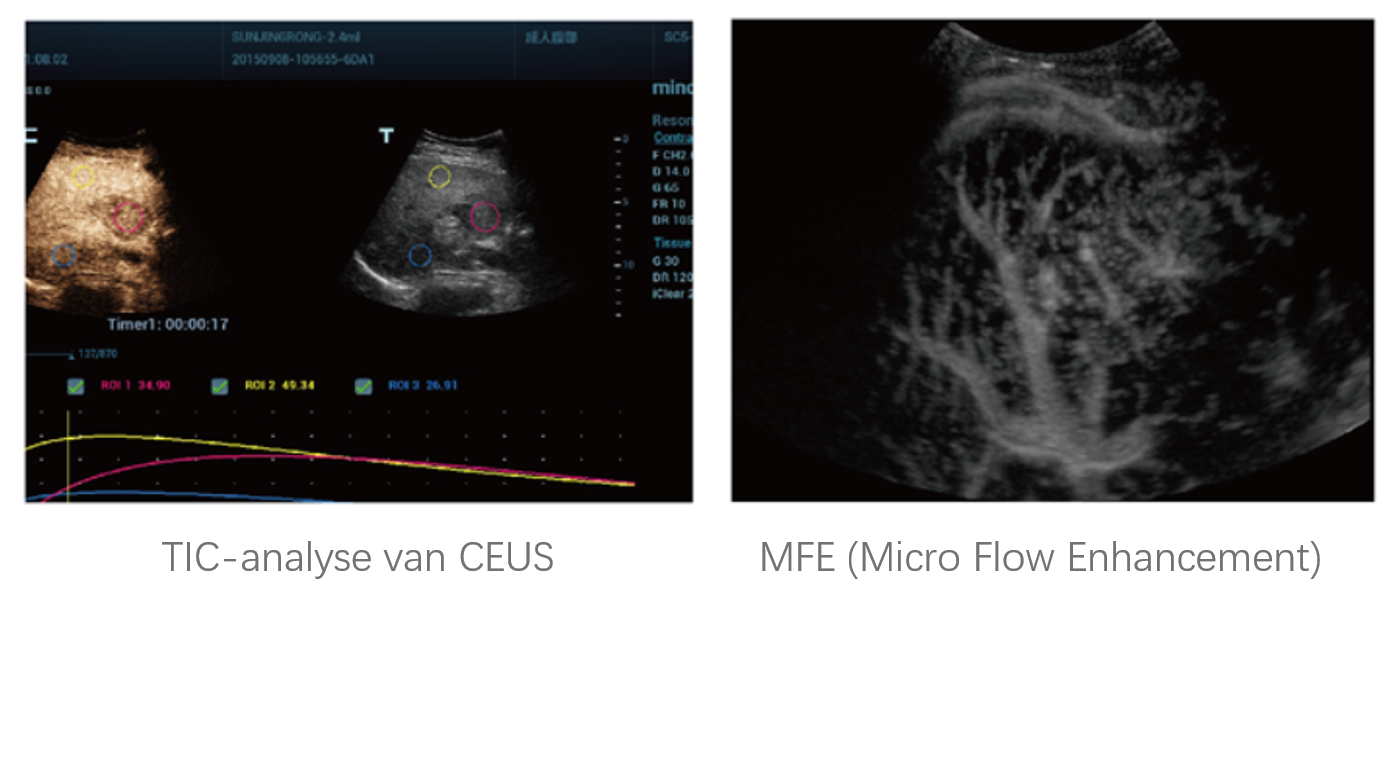

Sinds de oprichting van het bedrijf is Mindray voortdurend op zoek naar nieuwe manieren om het diagnostisch vertrouwen te vergroten. Resona 7 wordt aangestuurd door de meest revolutionaire ZONE Sonography?-technologie. Zijn nieuwe ZST+-tilt de kwaliteit van ultrasoundbeeldvorming naar een hoger niveau door middel van zoneacquisitie en kanaalgegevensverwerking.

Naast de hoogwaardige beeldvormingskwaliteit verbetert de Resona 7 tevens de klinische onderzoeksmogelijkheden met de revolutionaire V Flow voor vasculaire hemodynamische evaluatie, en de intelligentste vlakacquisitie van een 3D-gegevenssets voor de diagnose van het foetale, centrale zenuwstelsel. Met zijn combinatie van de meest intu?tieve, op vingerbewegingen gebaseerde multi-aanrakingsbediening en alle essenti?le klinische functies loopt de Resona 7 voorop in de nieuwe golven van ultrasoundinnovatie.